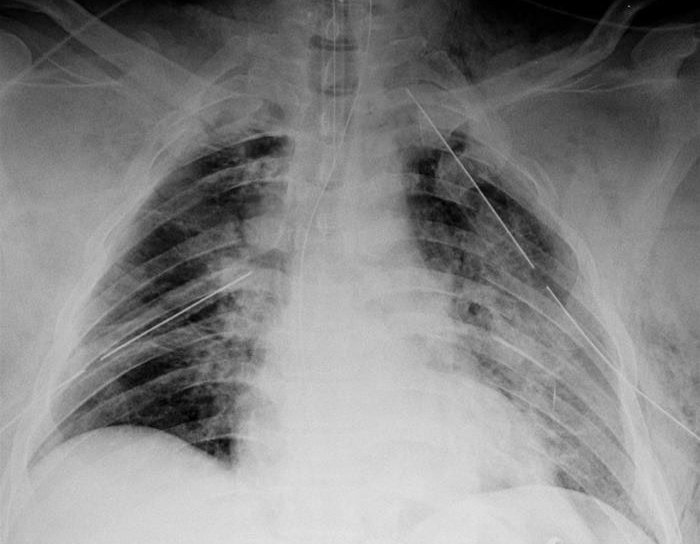

اجاك المريض وقالوا طلع من حادث اصطدام على خط سريع شو اول شي تفكر فيه بعد ما تشوف ال x ray؟

اجاك المريض عنده wheezing ولكن unilateral وعنده كمان hyperlucency مع ضيق بالتنفس وعنده هيك X-ray شو اول شي تفكر فيه؟ وكيف تعالجه؟

اجاك المريض عنده wheezing ولكن unilateral وعنده كمان hyperlucency مع ضيق بالتنفس وعنده هيك X-ray شو اول شي تفكر فيه؟

وكيف تعالجه؟